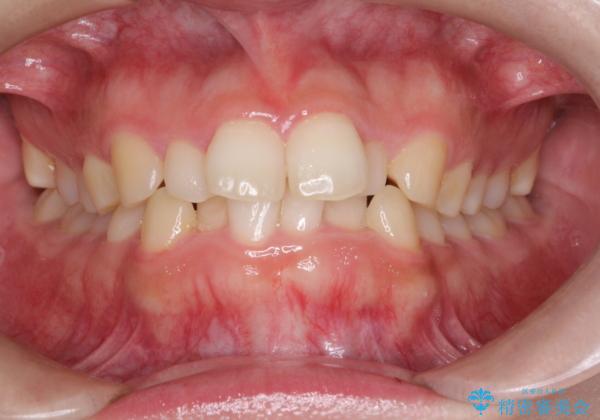

インビザラインでの前歯のガタガタの矯正

- 上下の前歯のがたつきを主訴に来院されました。

歯と歯の間をわずかに削りスペースを作り、インビザラインにて矯正治療を行うこととしました。

使用時間を守っていただけたので、スムーズに矯正を終了することができました。